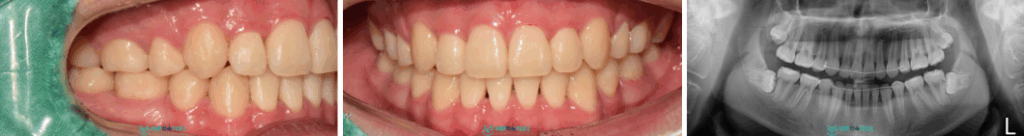

치료 마무리 후

위턱 오른쪽 견치가

제 위치에 바르게 자리 잡고

치열이 개선된 모습의

구강 내 모습과 파노라마 사진인데요.

환자분께서는

치과 공포증도 있으시다 보니

결과적으로 치료가 너무 잘 마무리되고,

웃는 모습이 자연스럽고 좋아지셔서

만족해하셨습니다.